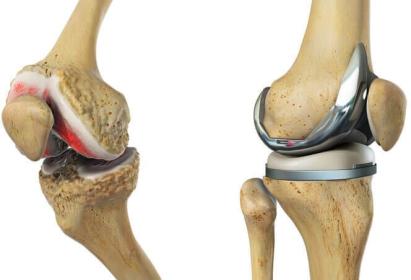

•artroplastika – zamjena zgloba odnosno ugradnja umjetnog zgloba je procedura kojim se zglob koljena zamjenjuje umjetnim dijelovima koji su izgrađeni ili od plastike ili od metala. Zamjena može biti djelomična ( parcijalna artroplastika ) ili potpuna ( totalna artroplastika, slika 24 ). Ovaj oblik operacije se uglavnom provodi kod starijih pacijenata ( dob preko 50 god ili starije ) sa teškim oblikom OA. Naknadna ista operacija je ponekad nužna ukoliko se ugrađena proteza s vremenom potroši, no sa današnjim tehnološkim napretkom i sve kvalitetnijim materijalima kao i konačnim proizvodom ( umjetnim zglobom ), proteze mogu trajati i preko 20 godina. Operativni zahvat nosi i određene rizike no rezultati su uglavnom jako dobri.

Slika 24.